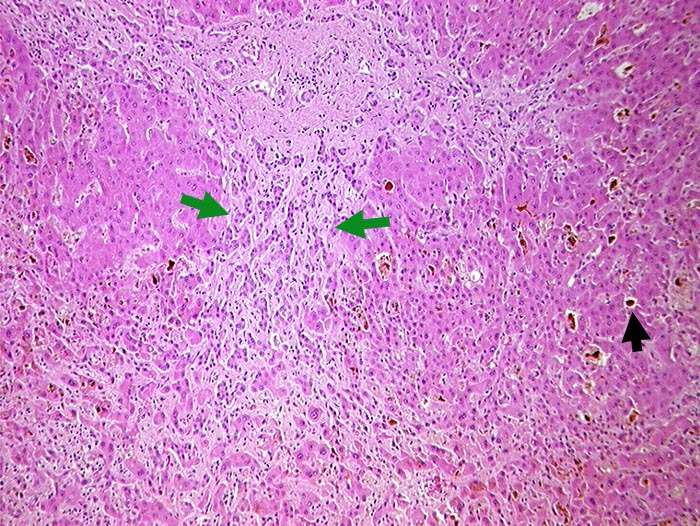

Extrahepatischer Verschlussikterus

Gallezylinder in erweiterten interzellulären Canaliculi (Gallethromben). Ductulusproliferationen im leicht fibrosierten Portalfeld.

Gallenblasenkarzinom. Kompression des Ductus choledochus durch Lymphknotenmetastasen im Leberhilus.